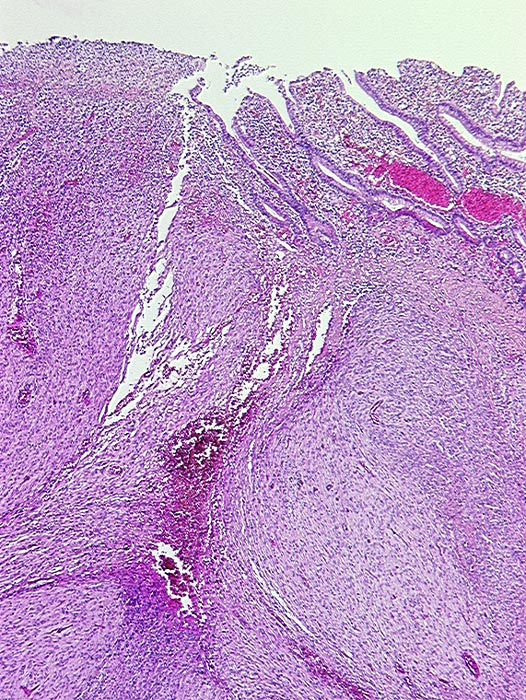

Ulzerierter gastrointestinaler Stromatumor (GIST)

Spindelzelliger von der Submukosa ausgehender Tumor. Links im Bild ist die Schleimhaut exulzeriert.

Metastasierender GIST. S-100 negativ, SM-Actin herdförmig positiv, CD 117 (c-kit) positiv.